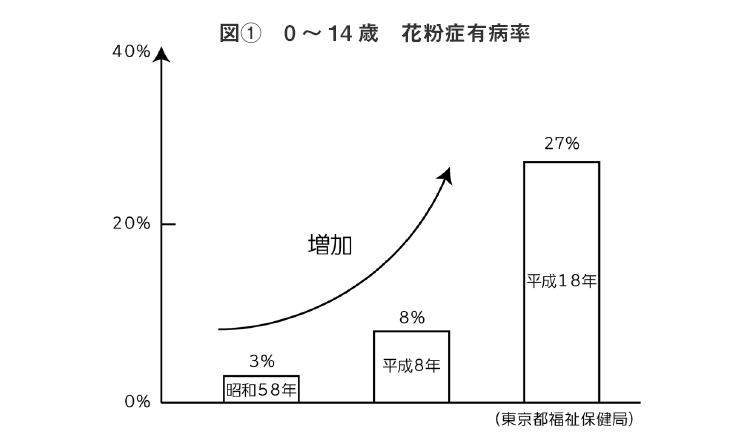

2013年 ロート製薬の3475人を対象に行った調査では、子供の3人に一人が花粉症を発症し、その8割が10歳前に発症しているという報告があります。

(図①参照)